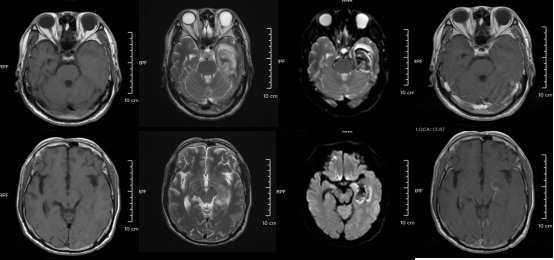

某单纯疱疹病毒性脑炎患者的医学影像。图源:浙江大学医学院附属第二医院

但如果拖延治疗,甚至会引发脑炎,可能出现癫痫、肢体偏瘫、尿潴留、认知功能障碍等严重后遗症,恢复时间长达3-6个月,甚至影响终身。